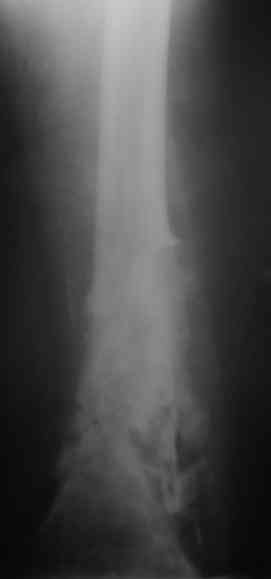

Уважаемые коллеги! Пациент лечился по поводу перелома н/3 бедра 1 год назад.

В настоящий момент: Несросшийся перелом н/3 правого бедра. Остеомиелит, свишевая форма. Контрактура коленного сустава.

Из свища скудное гнойное отделяемое. Как минимизировать количество операций, максимально улучшить качество жизни, сократить время пребывания в аппарате внешней фиксации, т.е. вернуть больного к нормальной жизни за минимальное количество ходов?

Да, стоит наверное добавить, что у нас отсутствует ЭОП. Как вы оцените следующую тактику: санация - антеградная установка спейсера на сплошном штифте + внешняя фиксация на 2 месяца - восстановление объема движений в коленном суставе?